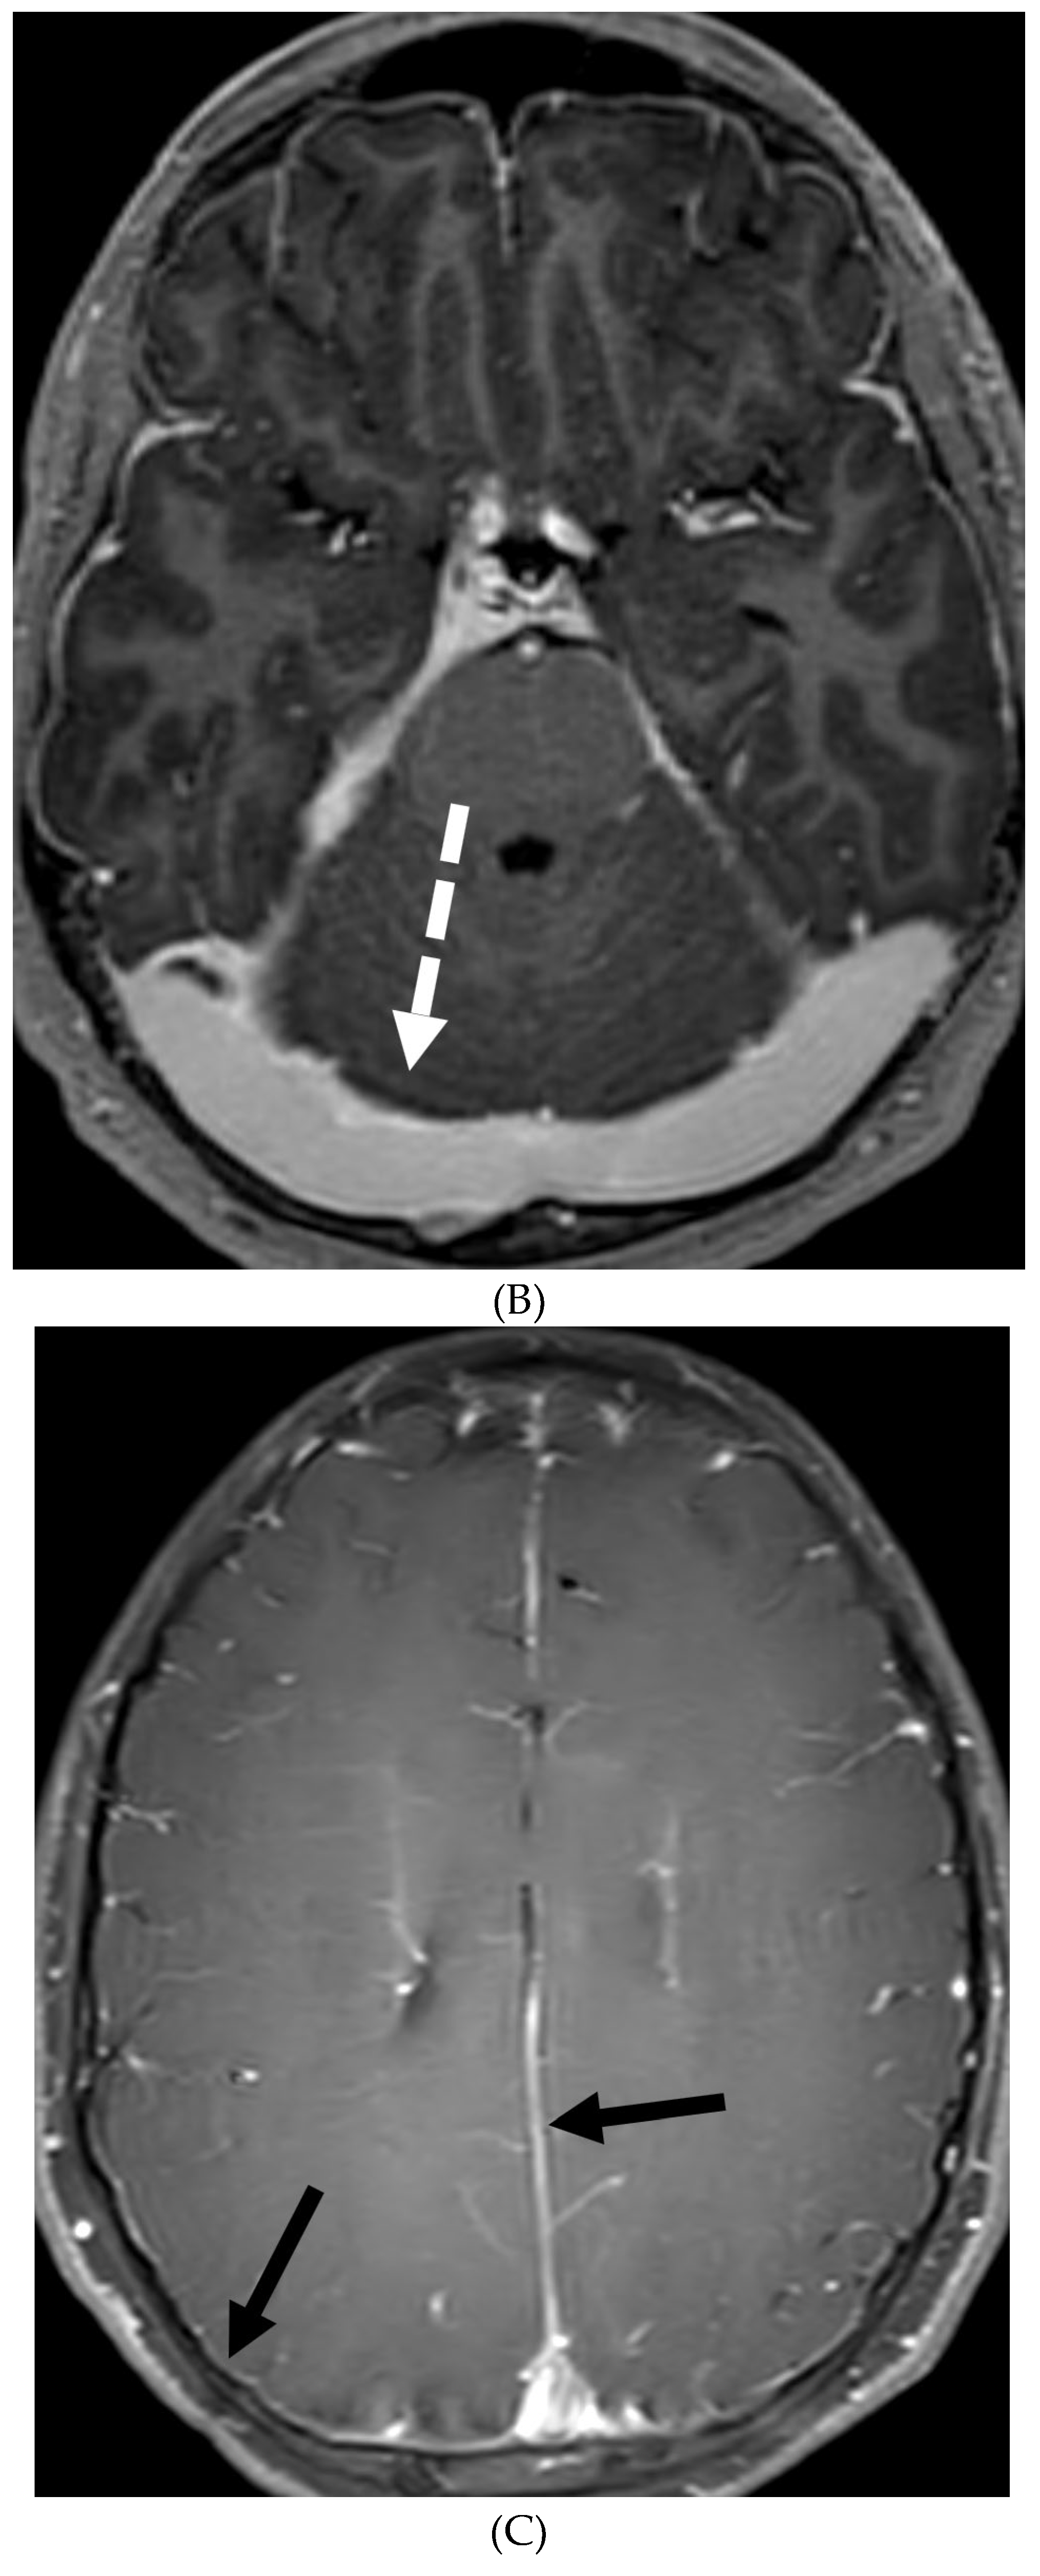

INTRACRANIAL HYPOTENSION (IH)

- Peterson EE, Riley BL, Windsor RB. Pediatric Intracranial Hypotension and Post-Dural Puncture Headache. Semin Pediatr Neurol. 2021 Dec;40:100927. Epub 2021 Sep 3. PMID: 34749914. [CrossRef]

- Schievink WI, Maya MM, Louy C, Moser FG, Sloninsky L. Spontaneous intracranial hypotension in childhood and adolescence. J Pediatr. 2013 Aug;163(2):504-10. Epub 2013 Feb 28. PMID: 23453548. [CrossRef]

- Shah LM, McLean LA, Heilbrun ME, Salzman KL. Intracranial hypotension: improved MRI detection with diagnostic intracranial angles. AJR Am J Roentgenol. 2013 Feb;200(2):400-7. PMID: 23345364. [CrossRef]

- Yuh EL, Dillon WP. Intracranial hypotension and intracranial hypertension. Neuroimaging Clin N Am. 2010 Nov;20(4):597-617. PMID: 20974378. [CrossRef]

- Medina JH, Abrams K, Falcone S, Bhatia RG. Spinal imaging findings in spontaneous intracranial hypotension. AJR Am J Roentgenol. 2010 Aug;195(2):459-64. PMID: 20651205. [CrossRef]